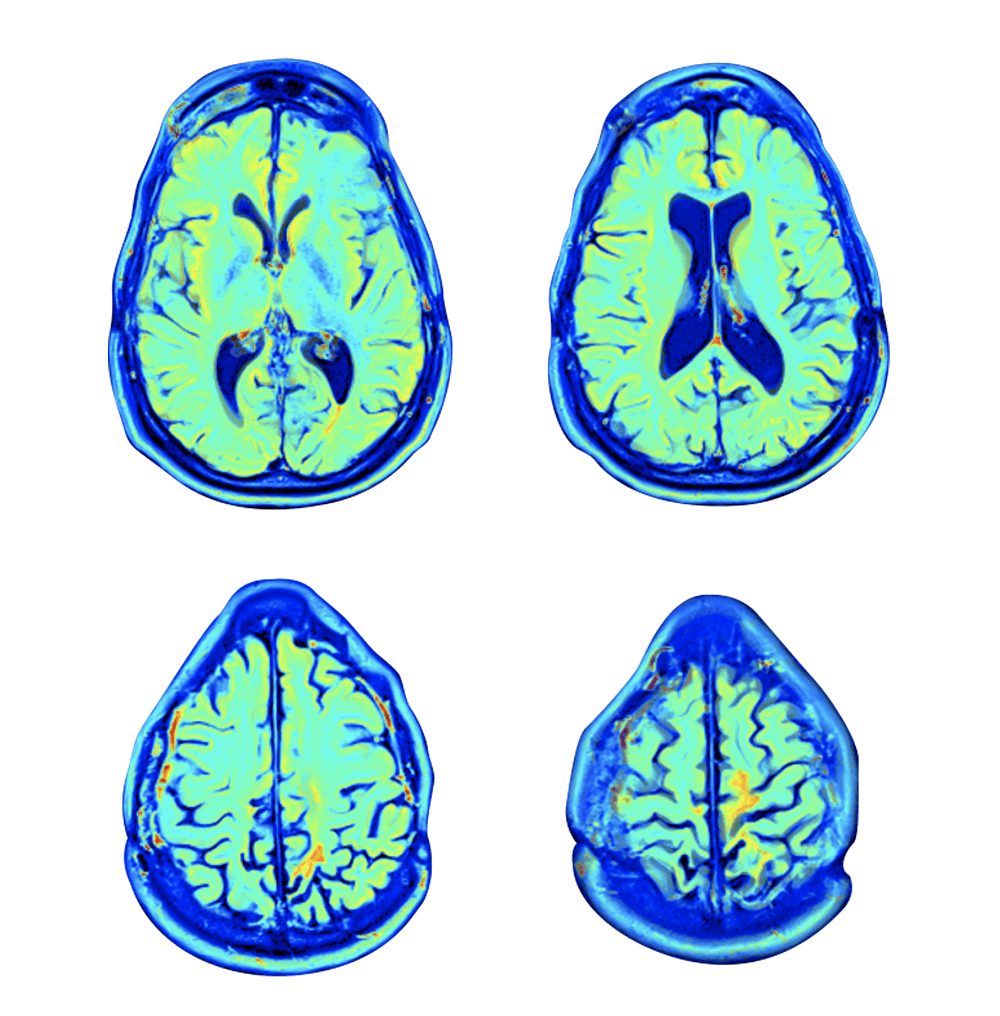

تدمر إصابات الدماغ الرضحية الدماغ عن طريق تعطيل أو تقييد تدفق الدم إلى مناطق معينة من الدماغ، مما يؤثرعلى قدرتها على العمل بشكل صحيح.

وجدت الدراسة أن المشاركين في مجموعة العلاج شهدوا تحسناً ملحوظاً في الوظائف الإدراكية والذهنية، وتحسينًا في الذاكرة والوظائف التنفيذية بعد خضوعهم للعلاج بالأكسجين عالي الضغط. كما شهدوا تغييرًا إيجابيًا في بنية الدماغ وارتفعت درجات الفهم العاطفي في جوانب القلق والاكتئاب وغيرها.